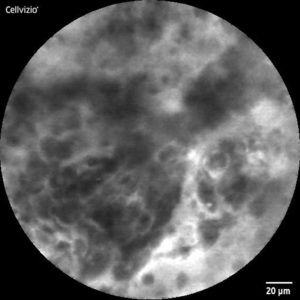

CLE-Image of healthy (l) and malignant (r) tissue

To improve data quality, I carefully processed the images by removing artifacts and low-quality samples and applied data augmentation to balance the classes. After this step, the final dataset was composed of 7,997 images labeled as neoplastic and 8,142 labeled as healthy tissue by a medical professional.